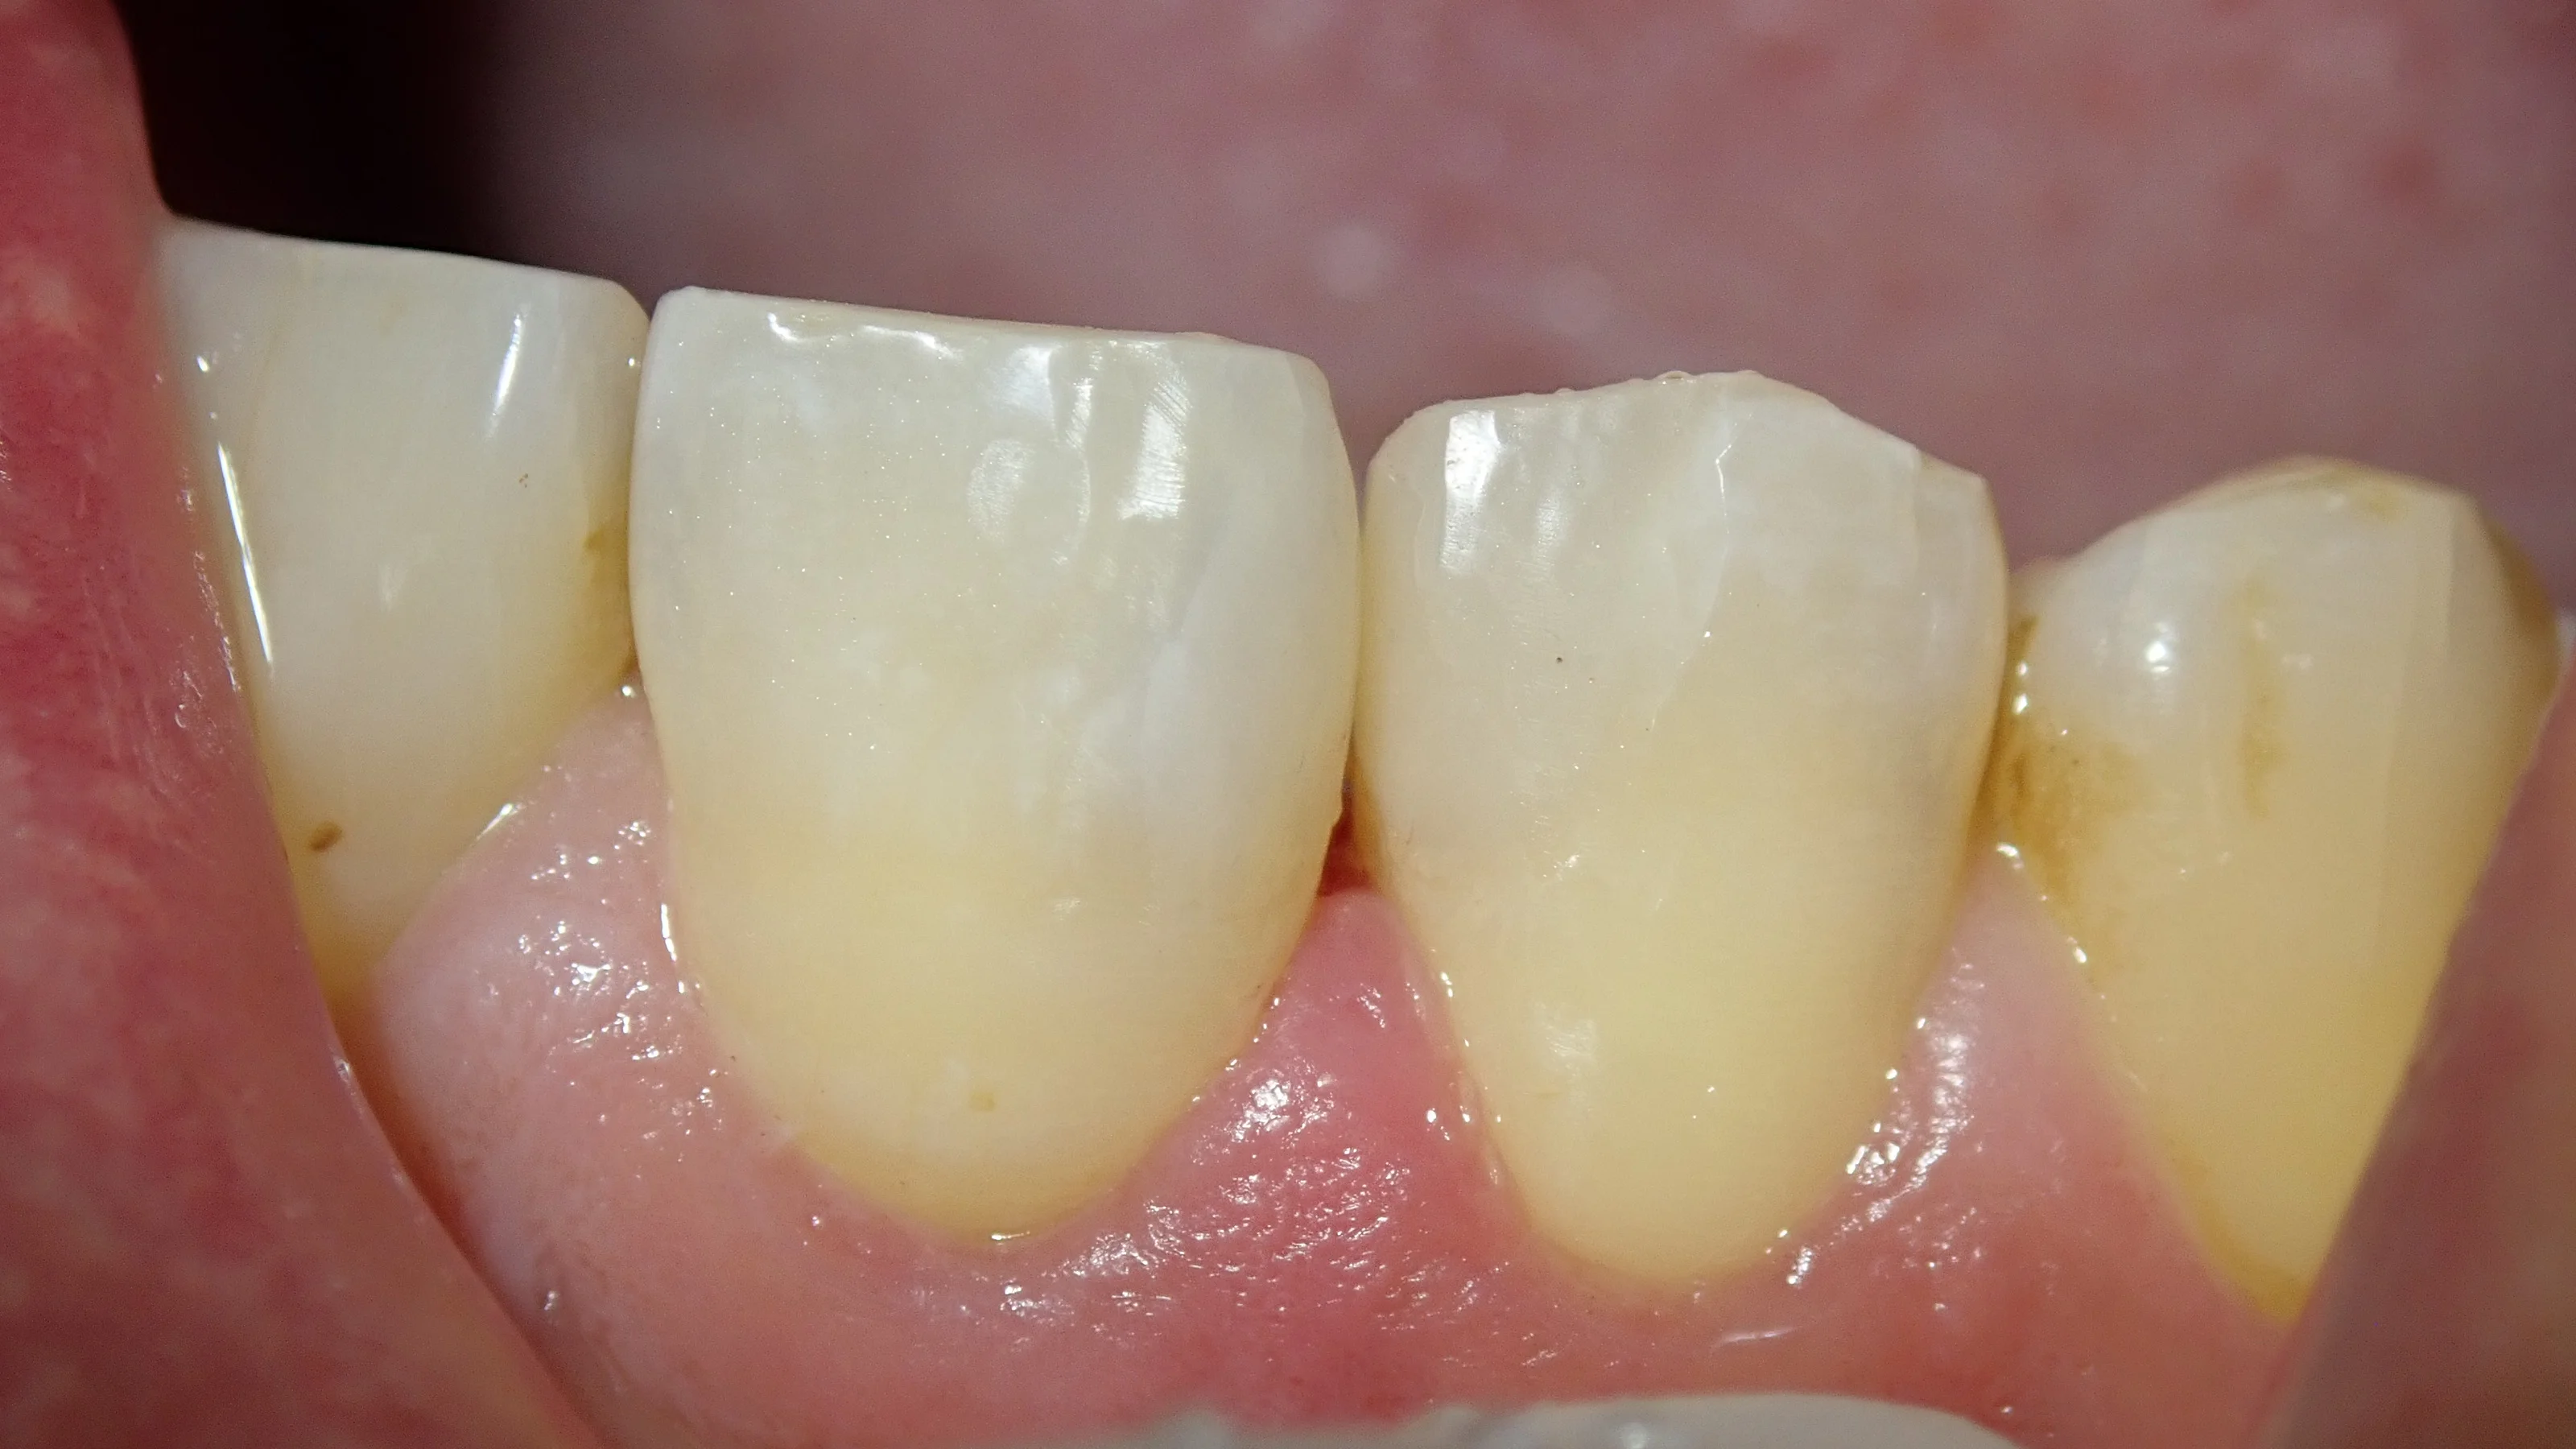

例えば、この方なんですが・・・

前歯の詰め物が割れたって言って来られたんですが、実際は割れたのではなく、虫歯で外れたって感じでした。

裏側から見た写真がこちらです。

掛けたところの左側にある歯も詰めている部分が黒くなっているのがなんとなくわかるかと思います。